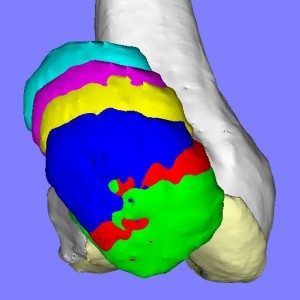

膝蓋骨脱臼には様々なパターンがあり、患者それぞれの膝蓋骨の動きのパターンを評価して適切な手術方法を検討します。

膝蓋骨の動きには上図のように様々なパターンが存在します。(我々の研究結果から)